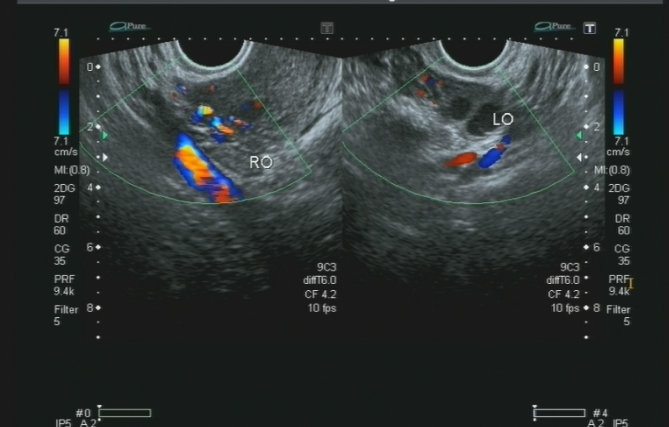

B超

其原理是通过发射超声波并检测回声,判断脏器距离与性质。其优点包括:无放射性伤害、探头灵活移动实现多角度成像与动态血流观察、即时检查结果且可重复、设备轻便易操作便于床旁检查。然而,其缺点是缺乏特异性,需结合其它症状与检查确诊。

(上腹部超声影像)